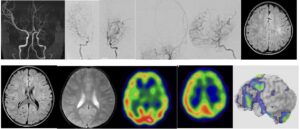

2025年2月 74歳女性のバイパス術を行いました。今年初めに立てた医局の目標は「手術件数300件以上」「一人一本論文執筆」「3名の博士号」「一名の入局者」です。手術に関しては医局員一同が毎日患者を治すため奮闘努力しており、献身的な働きに感謝しかありません。でも手術が増えると麻酔科医の負担も増えるもの。麻酔科負担を減じるため手術時間短縮する努力を命じています。このバイパスも16時には終了すると目標をたて、血管を2本つなぎ(ダブルバイパス)、目標通り完遂することができました。患者さんも安定してます。手術を過度に急ぐ必要はありませんが、無駄な操作は省き、キビキビ手術するよう心がけなければいけません。術前CVRがマイナス(steal)であったため厳密な血圧管理をしてもらい、術後一過性の構音障害が出ましたが、それも消失し、後遺症なく退院されました。

STA-MCAバイパスを行いました